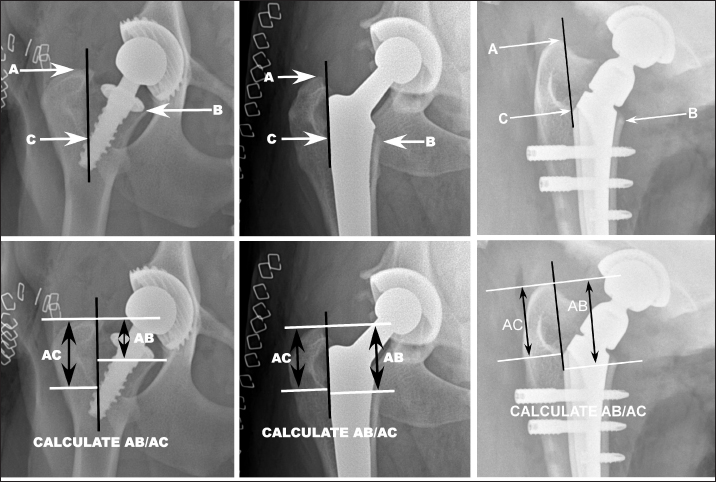

The level of the osteotomy was evaluated by first creating a vertical reference line (VRL) that was defined distally by the most distal medial aspect of the intertrochanteric fossa (point C; Fig. 1). The proximal end of the line was defined by making the line tangential to the medial aspect of the greater trochanter. Three points were then identified on the proximal femur. The most proximal aspect of the greater trochanter was identified (point A) and a line perpendicular to the VRL was drawn through this point and accordingly named line A. Next, the most distomedial aspect of the femoral osteotomy was identified (point B). A line perpendicular to the VRL was established through this location and was named line B. Lastly, a line perpendicular to the VRL was established through the most distal medial aspect of the intertrochanteric fossa (i.e., point C), and was named line C. The distances between lines A and B and A and C were measured and the ratio of the length AB to AC was calculated (AB/AC ratio; effectively the ratio of the distance from the greater trochanter to the femoral osteotomy relative to the distance between the greater trochanter and the distal aspect of the intertrochanteric fossa). Larger ratios were consistent with a more distal osteotomy and small ratios were indicative of a more proximal osteotomy.

Fig. 1. A VRL (black) was defined distally by the most distal medial aspect of the intertrochanteric fossa (point C). The proximal end of the line was defined by making the line tangential to the medial aspect of the greater trochanter. Three points were then identified on the proximal femur. The most proximal aspect of the greater trochanter was identified (point A) and a line perpendicular to the VRL was drawn through this point and accordingly named line A. Next, the most distal-medial aspect of the femoral osteotomy was identified (point B). A line perpendicular to the VRL was established through this location and was named line B. Lastly, a line perpendicular to the VRL was established through the aforementioned point C, the most distal medial aspect of the intertrochanteric fossa, and was named line C. The distances between lines A and B and A and C were measured and the ratio of the length AB to AC was calculated (AB/AC ratio). Larger ratios were considered consistent with a more distal osteotomy and small ratios were considered indicative of a more proximal osteotomy. Representative images of Helica (far left), BFX (middle), and Zurich (right) THRs are included.